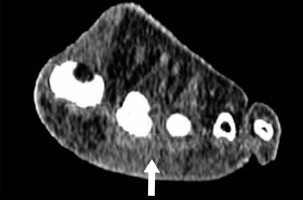

Each CT was reviewed retrospectively by two fellowship-trained Musculoskeletal Radiology Consultants who were blinded to the ultrasound reports. The CT’s were all performed on a Siemens Somatom Sensation 4 (Siemens, Erlangen, Germany) (2007-2014) and Siemens Somatom Sensation AS (Siemens, Erlangen, Germany) (2014-2019) with spiral acquisition and 1.25 mm axial slices. Multi-planar reformats in the long axis parallel to the metatarsal shaft and short axis perpendicular to the metatarsal shaft were obtained. The images were reviewed on both soft tissue and bone windows. The presence or absence of a MNBC and its size and position was recorded. A MNBC was suspected when there was soft tissue density in the web spaces with obliteration of the fat.

Figures 1 and 2 demonstrate the appearance of MNBC on CT and MRI.